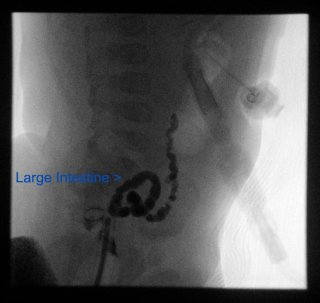

We had misunderstood what we’d been told about the placement of the line. The azygus vein is not a central vein. That means, it doesn’t directly connect to the heart. The tip of the new line is in a dilated part of that vein. But, after the tip there are some collateral (spiderlike veins that grow around a clot to reroute bloodflow like the little streams that form around the sides of a river if it is partially blocked.) And it is those that are connecting to the main veins and to the heart.